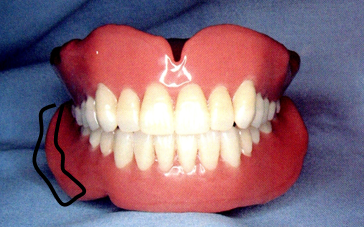

临床上,根据无牙颌每个解剖部位的不同特点,全口义齿制作时都要做相应的特殊处理,这与全口义齿的固位、稳定、美观、功能等都息息相关。

无牙颌的分区:

①主承托区:垂直于颌力受力方向的区域。包括牙槽嵴顶、腭部穹隆区、颊棚区等,该区不易出现骨吸收,能承担咀嚼压力。

②副承托区:与牙合力受力方向成角度的区域。包括上下颌牙槽嵴顶的唇、颊和舌腭侧(不包括硬区),与颊舌的界限在粘膜和口腔前庭黏膜反折线,支持能力较差,不能承受较大压力,只协助主承托区承受咀嚼压力。

③边缘封闭区:义齿边缘接触的软组织部分,如黏膜皱襞、系带附着部、上颌后堤区和下颌磨牙后垫。

此区有大量疏松结缔组织,与义齿边缘紧密贴合,防止空气进入基托与组织之间,产生良好的边缘封闭作用,从而形成负压和吸附力保证义齿固位。

④缓冲区:无牙颌上的颧突、上颌结节的颊侧、切牙乳突、下颌隆突、颌舌骨嵴,牙槽嵴上的骨尖、骨棱等部位。这些部位粘膜较薄,基托相应部位应磨除少许做缓冲处理。

⑤后堤区: 腭小凹后方,轻压颤动线以获得良好的封闭。